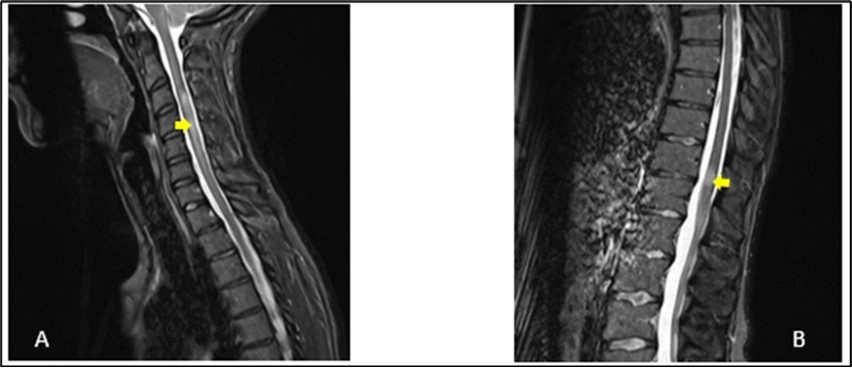

A 27-year-old girl presented at the emergency department, at a hospital in the Paris region on March 9, 2020 with complaints of left interscapular pain, paresthesias and weakness in the ipsilateral upper limb. These symptoms followed paresthesias on the fingertips of her right hand the day before her admission. She did not report fever, sphincter disorder or gait disturbance. No eye symptoms reported. In her medical history, she was treated two weeks earlier for pneumonia with COVID-19. There was no another previous infectious episode apart from the COVID-19. She had no history of diabetes, hypertension, cerebrovascular disease or migraine. She had not history of multiple sclerosis or Neuromyelitis Optica Spectrum Disorder (NMOSD). There was no history of smoking, contraception drugs intake or any prolonged drug intake. On the first examination in the neurology department where she was transferred on the same day of her admission, she had good general condition and was apyretic. She had a pulse rate of 74/min and the blood pressure was at 130/80 mmHg. The neurological evaluation showed on the left side, a muscular weakness grade 4 in the proximal part and grade 3 in the distal part of upper limb, and in the lower limb, the weakness graded at 3 in the distal part, using the Medical Research Council Scale (MRC) for muscle strength. There was no weakness on the right side. Deep tendon reflexes in both left and right were normal. Babinski sign was found on the left side. She presented tactil and algic hypoesthesia in the lower left limb ascending until the C4 level in the left side. There was no perineal sensitive trouble. The remain neurological exam including, higher functions, cranial nerves, was with no particularity. Otherwise, cardiovascular and respiratory systems examination were within normal limits. Blood laboratory tests were within the normal ranges, including complete blood count (CBC), C-Reactive protein, renal and liver functions and blood serum ionogram. Human Immunodeficiency Virus (HIV) tests including p24 antigen and antibodies to HIV were negative. Syphilis serology and Aquaporin 4 antibody were also negative. Encephalic Magnetic Resonance Imaging (MRI) demonstrated scattered hyperintense lesions on FLAIR imaging in deep hemispheric and juxtacortical white matter in supratentorial and in infratentorial floors (Figure 1). Medullary MRI showed T2 hyperintense lesions in left cervical hemi-marrow extending from C3 to C6, at T3, T4, T11 and T12 levels (Figure 2). These lesions were not enhanced after injection of gadolinium. The Cerebrospinal fluid (CSF) appeared to be colorless and clear with no cell detected microscopically; cerebrospinal protein level, 0.4 mg/L, glucose (Glu) level, 3.2 mmol/L; and instant blood glucose level, 5.2 mmol/L. CSF bacterial culture demonstrated no growth after 3 days, and herpes simplex virus 1 and 2, varicella-zoster virus test was negative. Reverse transcription-polymerase chain reaction (RT-PCR) assay test for COVID-19 was negative in the CSF. The final diagnosis was an ADEM secondary to novel coronavirus (nCov) infection. She was given methylprednisolone (1000 mg IV per day for 5 days) followed by Intravenous Immunoglobulin (IVIG) therapy at 0.4 g/kg daily for 5 days. Together with chemotherapy, she received physiotherapy coupled with occupational therapy. The outcome was good with improvement of weakness and paresthesias. There was residual tingling on the fingertips of the left hand. The patient was discharge on day 13.

Figure 2.Sagittal T2-weighted spine MRI showing at cervical level (A), a spontaneous hyperintense lesion of 5 cm from C3 to C6 and at thoracic level (B), a spontaneous hyperintense lesion of 1.5 cm from T11-T12

We have described a case of ADEM post COVID-19 infection in a 27-year-old girl who was taken care of in a hospital in the Paris region. She was treated in the same hospital 2 weeks earlier for an acute respiratory distress syndrome caused by COVID-19 infection. The period of the study was at the beginning of the outbreak of COVID-19 infection in France. COVID-19 is a new entity caused by the severe acute respiratory syndrome coronavirus 2 (SARS CoV-2). It is known to cause respiratory complications, from mild upper respiratory symptoms to acute respiratory failure. ADEM is an immune-mediated inflammatory disorder of the CNS characterized by a widespread demyelination that predominantly involves the white matter of the brain and spinal cord. The condition is usually precipitated by a viral infection or vaccination 7. For this, it is also named post-infectious encephalomyelitis. The infection typically comes before the onset of symptoms of approximately 2 days to 4 weeks 8. This was the case of our patient who presented two weeks before the onset of neurological symptoms, a pulmonary infectious episode for which the etiological research revealed a COVID-19 infection. The pathological abnormalities during ADEM are post-infectious changes of immune origin affecting the central nervous system. These changes are present in the small blood vessels of both white and grey matters. As the lesions become older, the macrophages increase and lymphocytes decrease in number. At a late stage of disease foci of fibrillary fibrosis can also be seen in adjacent brain tissue. Although postinfectious encephalomyelitis typically involves the white matter, lesions in grey matter have also been seen and may involve basal ganglia and the thalamus 3, 4. Due to the impossibility to perform an anatomopathological examination in our patient, MRI of the CNS constitute a reliable tool to translate the diffuse CNS damages of the brain as well as of the marrow. These elements are well presented on the imaging performed by our patient (Figures 1, 2). There is a lack of detection in CSF in most cases besides evident inflammation. This raises the possibility that the majority of ADEMs associated with COVID-19 could be the result of immune-mediated mechanisms or molecular mimicry which generates an aberrant neuro-inflammatory loop, so the virus does not need to cross the blood-brain barrier to cause damage to the CNS 9. As with ADEM occurring after other viral infections, the mechanism would be the same in the case of COVID-19 infection. The presence or history of any other systemic infection, particularly viral, would have made the diagnosis unlikely. As the patient had no other infection apart from COVID-19 in the days preceding the neurological symptoms, it is therefore perfectly legitimate to consider this infectious episode as the trigger for the cascade of immune reactions at the origin of the neurological symptoms. In most cases, ADEM has a monophasic course and is self-limiting, with return to neurological baseline within 3 months after the onset of symptoms. Occasionally, a subset of ADEM patients with relapsing disorders, including recurrent disseminated encephalomyelitis (RDEM), multiphasic disseminated encephalomyelitis (MDEM), neuromyelitis optica spectrum disorders (NMOSD), and multiple sclerosis have been reported 10. The clinical presentation is heterogeneous. Typically, patients show prodromal symptoms such as fever, headache, malaise, nausea, and vomiting. The acute phase occurs with encephalopathy, characterized by altered behavior including irritability, confusion and consciousness like lethargy, stupor, or coma associated with multifocal or focal neurological deficits depending on the area involved in the demyelinating process 11. Other neurological findings have been reported in ADEM related to COVID 19. Laura Zelada-Ríos reported in 2021 pyramidal signs (44.4%), brainstem signs (11.1%), cerebellar signs (22.2%), seizures (33.3%) and peripheral nerve compromise (11.1%) 12. ADEM in COVID 19 pediatric patients have been also reported in children 6, 13. MRI plays a key role in the diagnosis of ADEM and should be performed as soon as it is suspected. The typical findings are identified as lesions with signal hyper-intensity in FLAIR and T2 sequences, they are usually multiple, asymmetric, irregular, poorly defined, and greater than 2 cm. In general, the white matter is affected, although it may involve the deep gray matter, the brainstem, the cerebellum, and the spinal cord 12. MRI is also used to consider differential diagnoses 14 multiple sclerosis (MS), neuromyelitis optica (NMO), and neuromyelitis optica spectrum disorder (NMOSD), which can overlap with ADEM in presentation 15. Among these previous diagnoses, multiple sclerosis remains the most important differential diagnosis of ADEM. Both clinically and paraclinically, these 2 pathologies share almost the same criteria. Thus, Swharz et al, in a cohort of 40 patients, fail to identify any exclusive feature characteristic of either condition. Similarly, cerebrospinal fluid findings are not distinctive enough to allow differentiation between ADEM and multiple sclerosis in a single patient. Even MRI studies were not able to differentiate ADEM from multiple sclerosis. Approximately, 50% of the patients with ADEM had MRI features that were suggestive of multiple sclerosis. however, fever, loss of consciousness, and meningism are infrequently observed but are highly suggestive of ADEM because these symptoms are rare in multiple sclerosis 16. It results from this study of Swharz, that the chronology of the neurological symptoms with a pre-existing systemic infection, viral especially constitutes a very determining profile. These data of the interrogation were at the base of the diagnosis of ADEM post covid of our patient more especially since there were no clinical or paraclinical arguments in favor of another potential differential diagnosis, that is Devic's neuromyelitis optica. Differences exist between encephalitis associated with COVID-19 and ADEM associated with COVID-19, one of them is temporality. Unlike ADEM, neurological symptoms usually appear simultaneously with respiratory symptoms in COVID-19-associated encephalitis. Brain inflammation expressed by pleocytosis is more frequent in encephalitis associated with COVID-19 17. Sharing the same pathophysiological mechanisms as other post-infectious encephalomyelitis, the principles of the treatment of post-COVID ADEM therefore remain similar. The treatment of ADEM is targeted to suppress a presumed aberrant immune response to an infectious agent or a vaccination. Treatment with intravenous corticosteroids (methylprednisolone) or adrenocorticotrophic hormone in large doses has been shown to improve the outcome 18, 19. Corticosteroids are usually associated with plasmapheresis and intravenous immunoglobulin. This association have been shown to produce dramatic improvement in some cases where corticosteroids have failed 16. In some cases, cytotoxic agents have been used with success 18. Functional rehabilitation as a support treatment is a useful contribution even if the publications do not usually mention it. Regarding clinical outcomes, it is generally favorable in the cases of ADEM. This was the case of our patient as well as the results reported by L. Zelada-Ríos et al. 12.